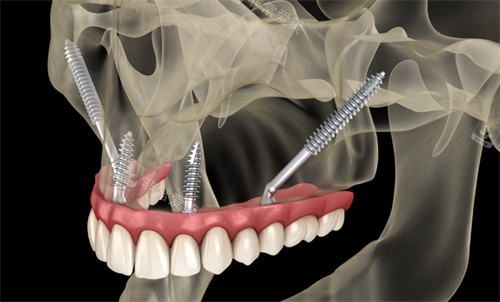

森朗口腔特别擅长穿颧穿翼种植技术,这是针对骨量重的不足患者的解决方案。

传统种植需要先植骨,等待6个月才能种植,而穿颧穿翼技术可以直接植入,大大缩短治疗周期!

正在进行的穿颧穿翼